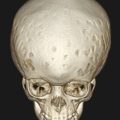

9.4.4 Nevoid Basal Cell Carcinoma Syndrome

When multiple KCOTs are present, the child must be further worked up for nevoid basal cell carcinoma syndrome (NBCCS), also known as Gorlin–Goltz syndrome. Keratocystic odontogenic tumors occur in 75% of patients with NBCCS. Keratocystic odontogenic tumors that occur as a part of this syndrome tend to have a higher recurrence rate.